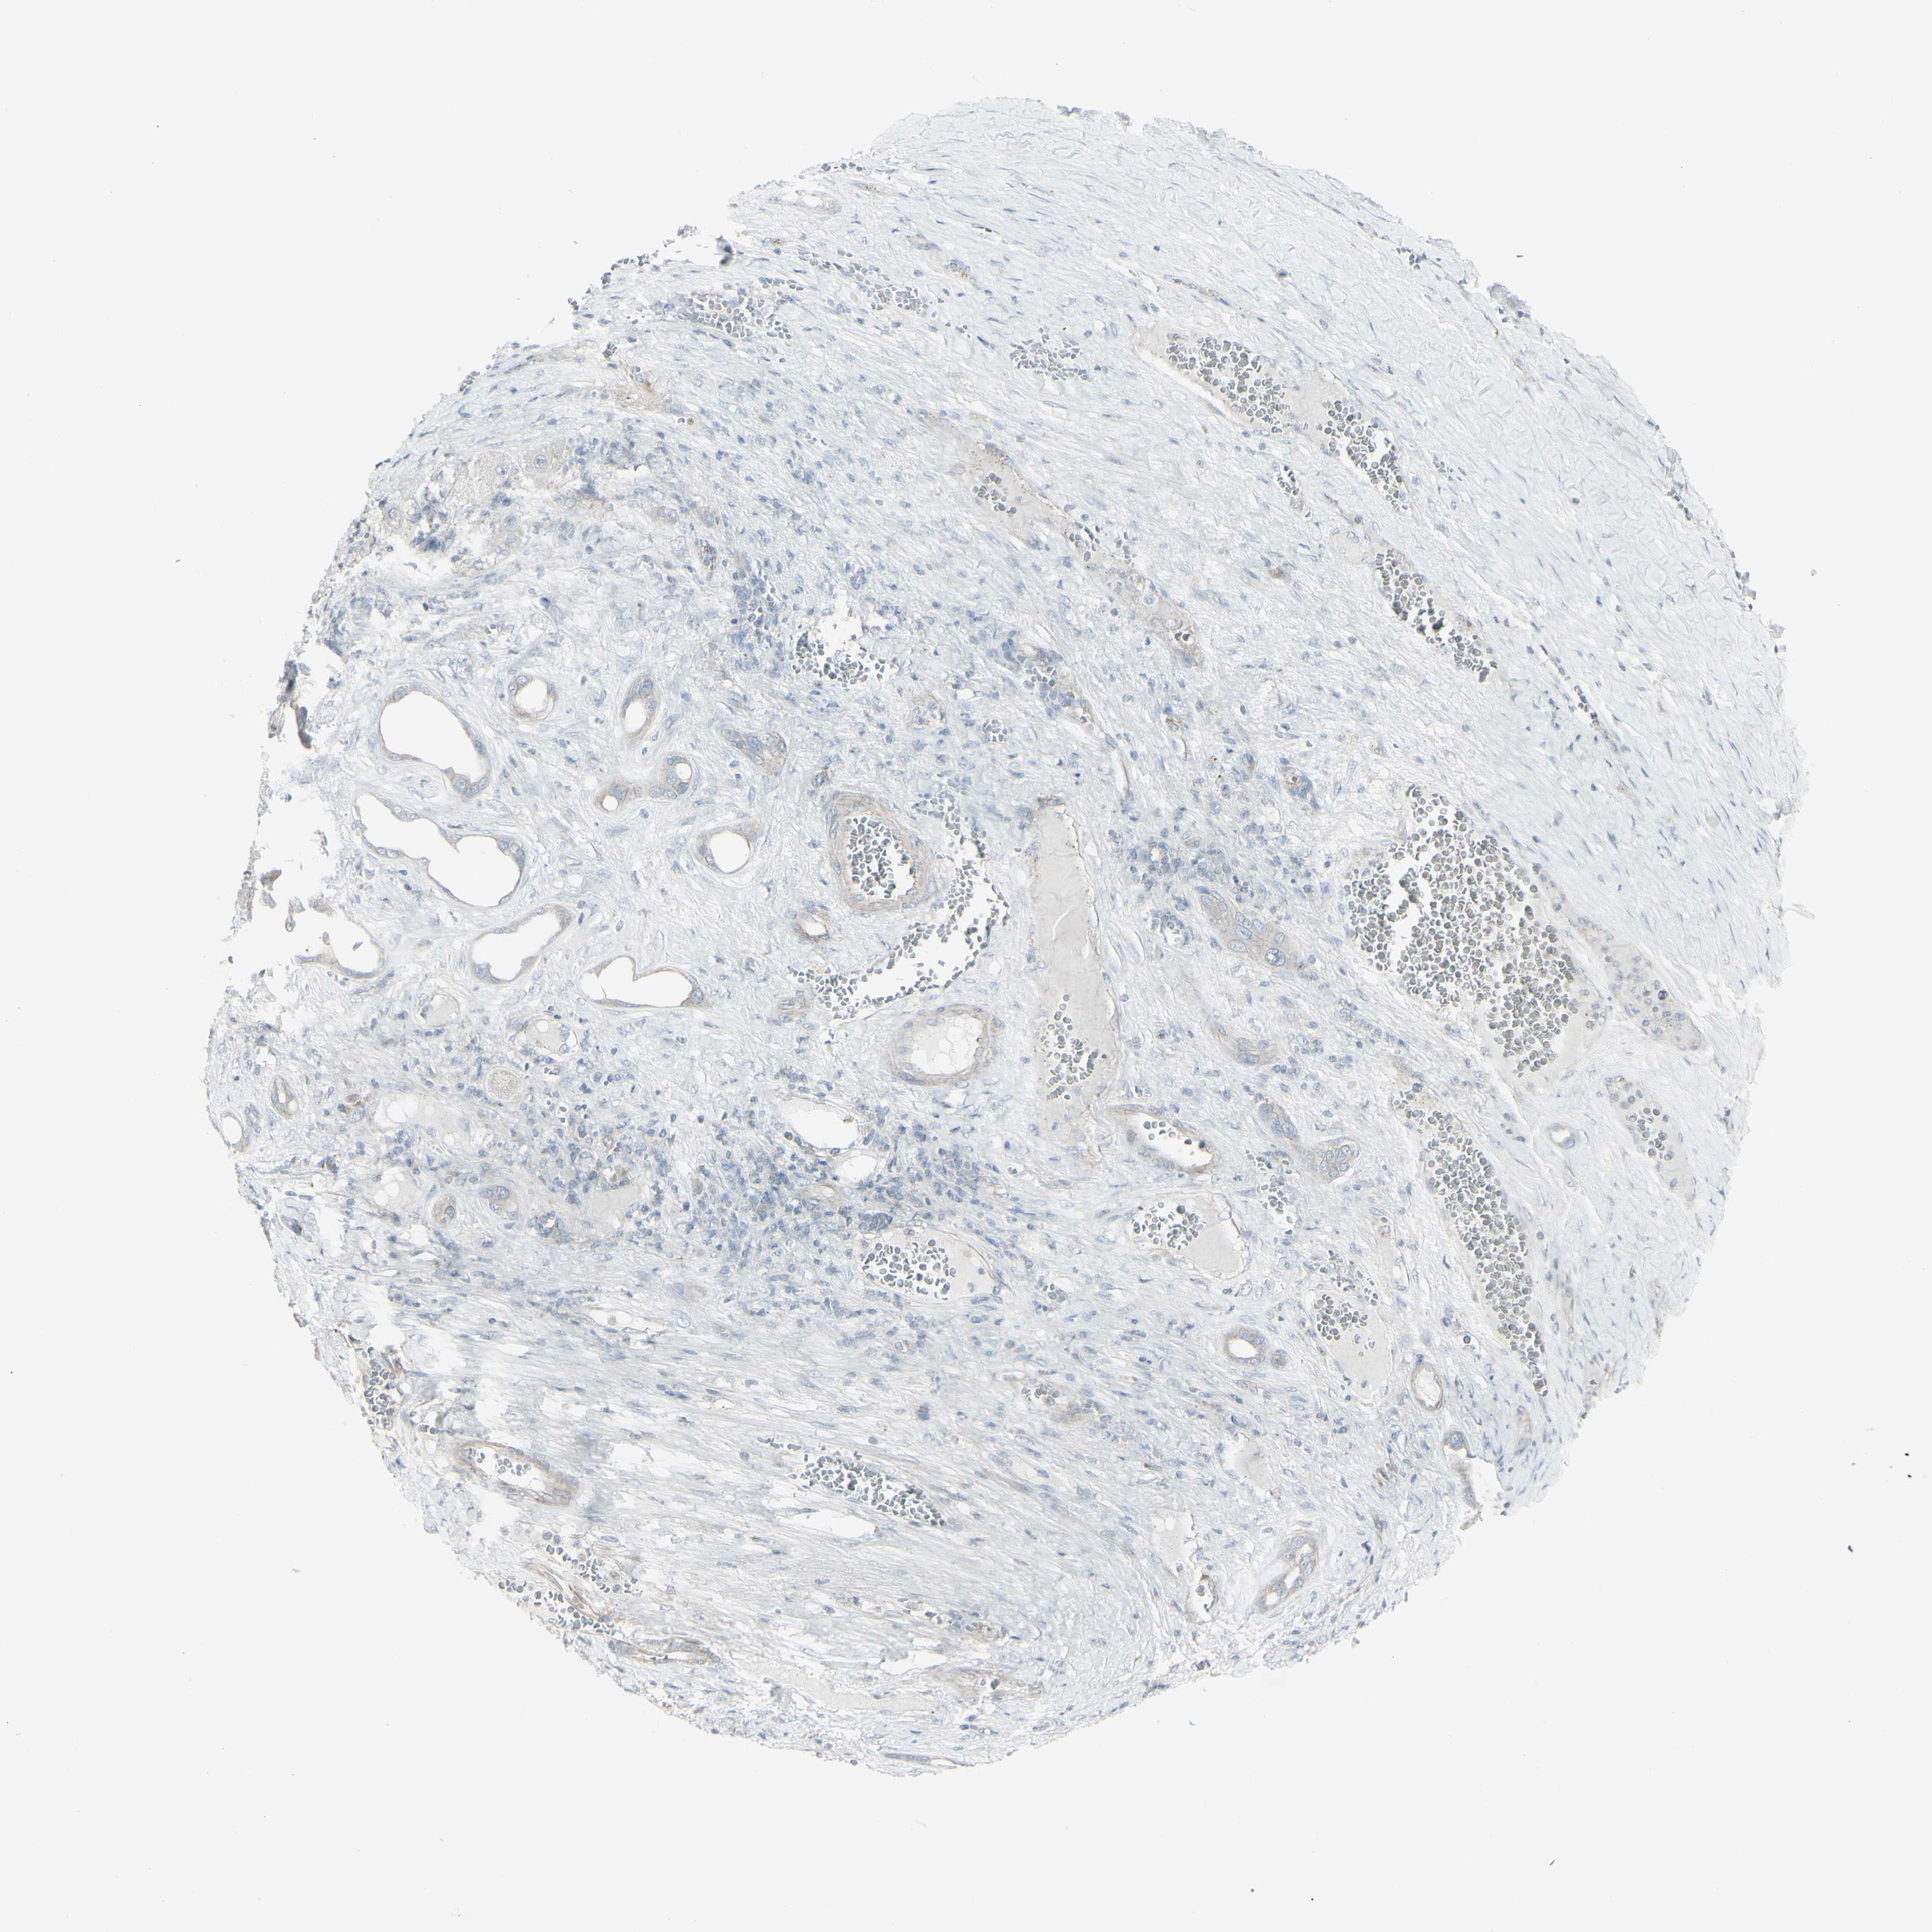

LIVER CANCER - Protein expressioni

A mouse-over function shows sample information and annotation data. Click on an image to view it in a full screen mode. Samples can be filtered based on level of antibody staining by selecting one or several of the following categories: high, medium, low and not detected. The assay and annotation is described here.

Note that samples used for immunohistochemistry by the Human Protein Atlas do not correspond to samples in the TCGA dataset.

Antibody stainingi

Antibody staining in the annotated cell types in the current human tissue is reported as not detected, low, medium, or high, based on conventional immunohistochemistry profiling in selected tissues. This score is based on the combination of the staining intensity and fraction of stained cells.

Each image is clickable and will lead to virtual microscopy that enables deeper exploration of all samples and also displays staining intensity scores, fraction scores and subcellular localization as well as patient and tissue information for each sample.

Antibody HPA011762

Antibody HPA017086

Staining

High

Medium

Low

Not detected

Intensity

Strong

Moderate

Weak

Negative

Quantity

>75%

75%-25%

<25%

None

Location

Nuclear

Cytoplasmic/membranous

Cytoplasmic/membranous,nuclear

Cholangiocarcinoma

Carcinoma, Hepatocellular, NOS